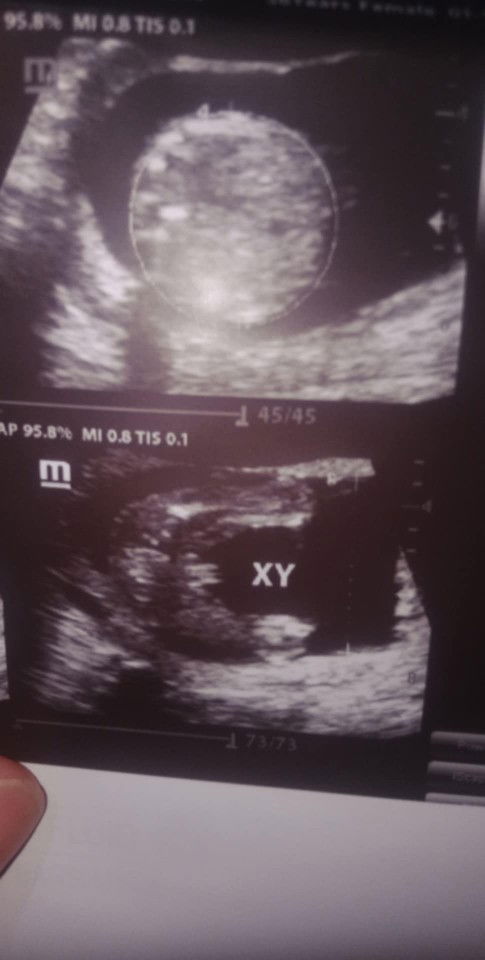

Gender 17 weeks

Nagpa pelvic ultrasound ako 17 weeks and 5 days,while doing the ultrasound tinanong ako ng ob sonologist kung gusto ko na daw malaman gender, I answered yes(kasi yun naman talaga purpose ko 😅) then sabi nya BOY daw, pero di ko tinanong kung sure n ba, na overwelm na kasi ako. Pag uwi ko sa bahay sabi ng kontrabida kong kapatid o bakit daw ang aga, baka daw mali result. Excited daw kasi ako 😅 kaya ngayon nacucurious tuloy ako kung BOY ba talaga. Gusto ko pa naman ng Baby Boy. Eto result ng ultraosund, ano po sa tingin nyo, boy po ba talaga? Respect my post. Salamat po sa sasagot. 😊